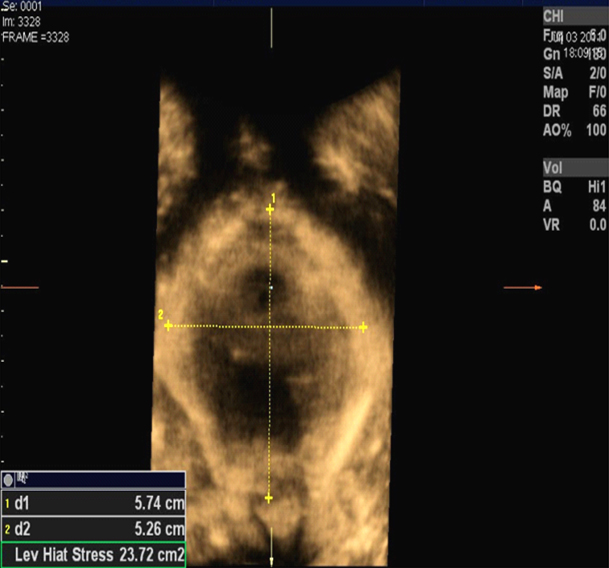

Transperineal Sonografi İncelemesi; supine veya erekt pozisyonda yapılır. 2D – 3D – 3D (TUI) – 4D (volume render) görüntüleme teknikleri pelvik taban anatomisinin ve pelvik taban hastalıklarının ortaya konmasında faydalar sağlamaktadır. Konveks prob (4 MHz – 6 MHz) ile perineal bölgeye minimal bası uygulanarak muayene yapılmalıdır. İmajlar istirahat halinde manevrasız ve Valsalva menavrası sonrasında cine-loop fonksiyon kullanılarak taranır. Valsalva sonrası mesane boynunda descensus (>30mm patolojik), Retrovezikal açı (maksimum 160 derece), Hiatal alan (maksimum 25cc) ölçülür.

Puborektalis kas travması (avulsion injury) pelvik taban kaslarının fonksiyonunu etkiler. Bu travması olan kadınların bir kısmında hiatal biometride değişiklik gelişebilir. Bu defektler palpable olmakla birlikte transperineal sonografik görüntüleme yöntemi ile objektif olarak defektin ortaya konulması, kesit planları üzerinde ölçüm yapabilme kolaylığını sağlar.